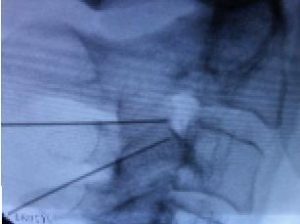

Comparação entre teste de provocação de disco (esquerda) e ressonância magnética (direita). Sem o resultado da provocação do disco no pré-operatório, o cirurgião não saberia qual o disco responsável pela dor nas costas (L4 / L5).